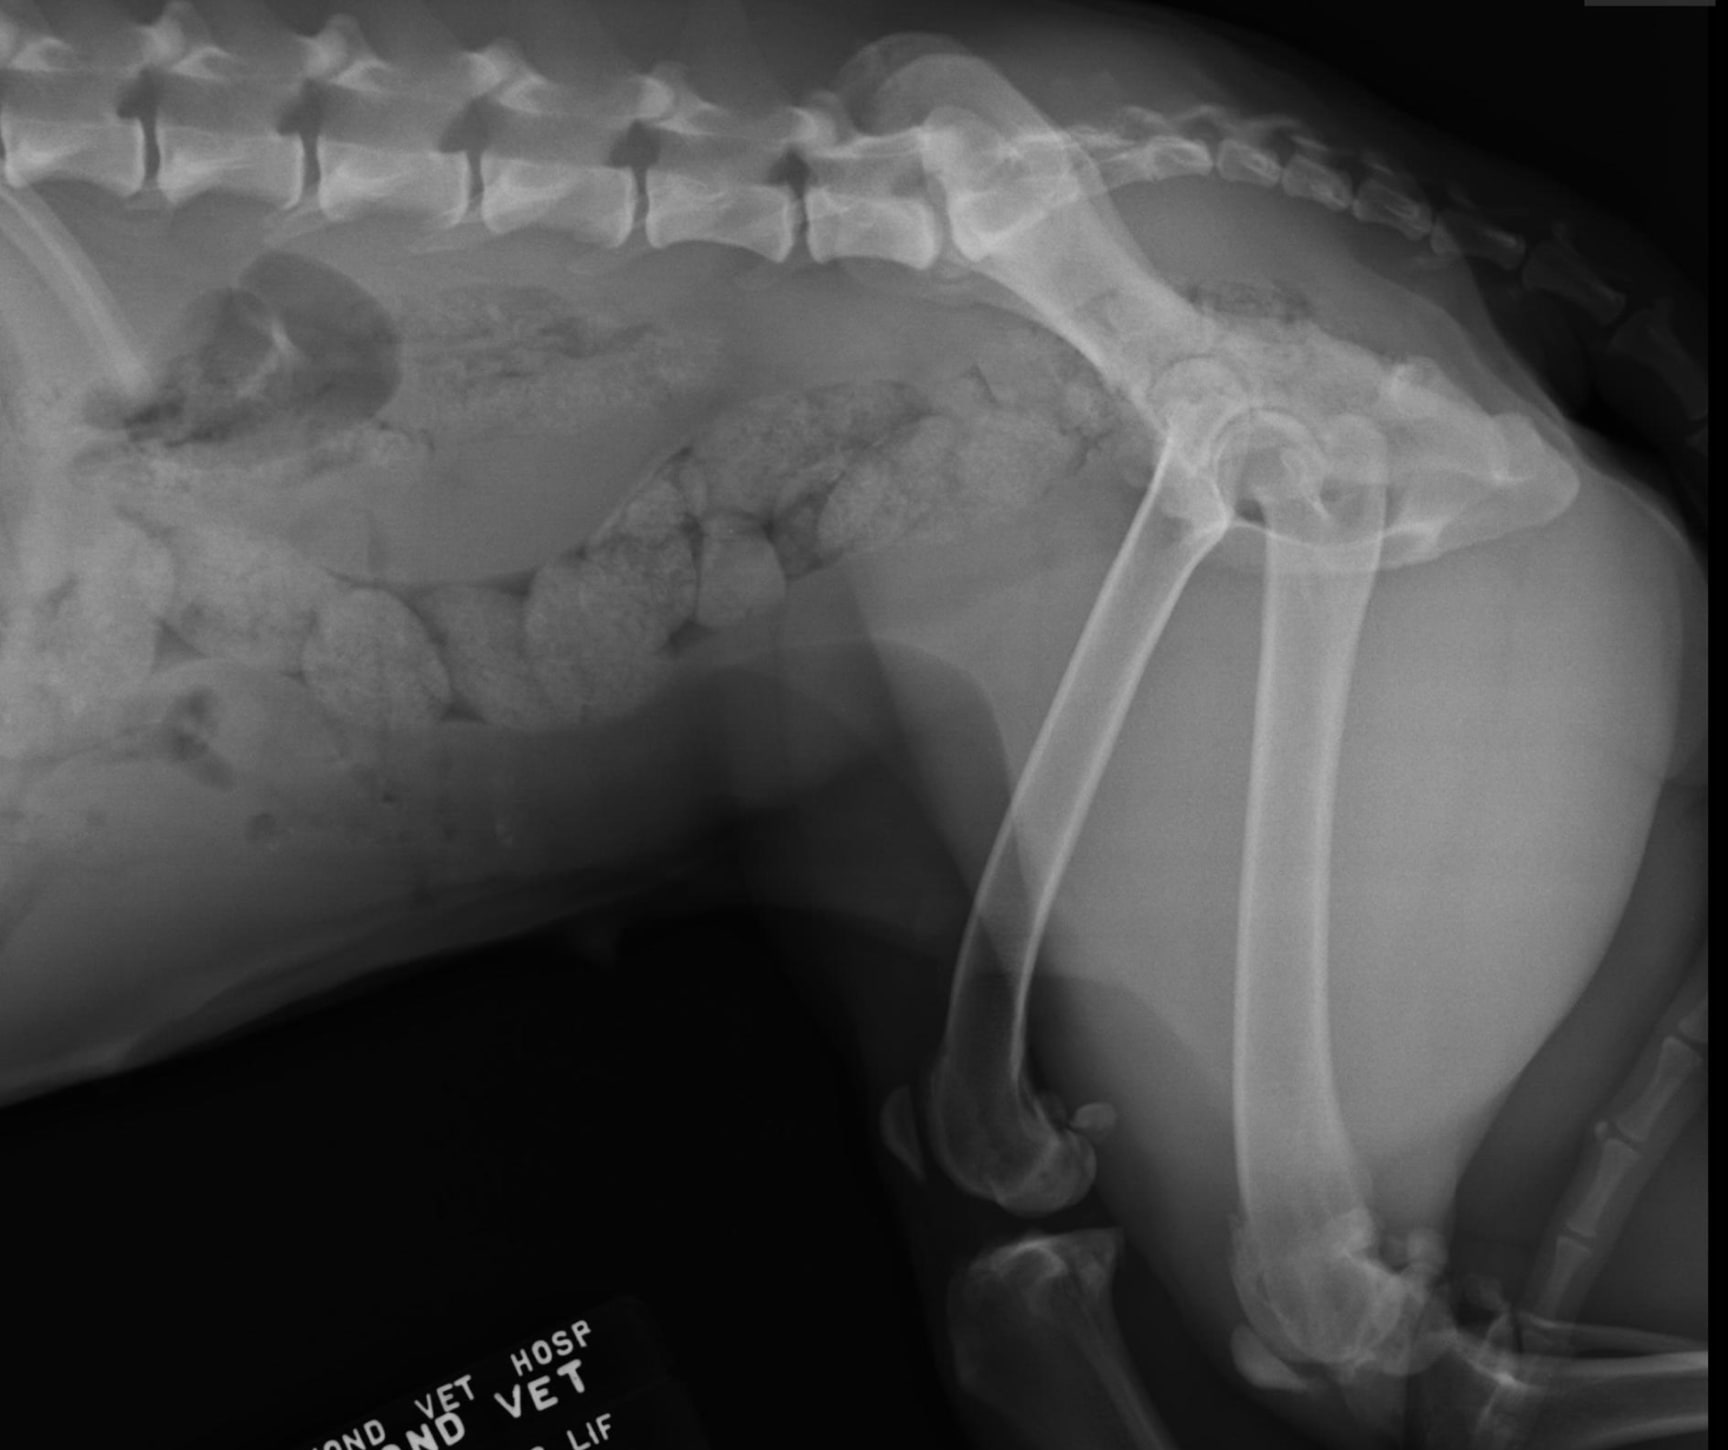

Hello, I was told that my 9 y/o girl has arthritis. She still fetches and climbs up and down stairs without signs of pain. Judging from the Xray, how are her hips and knees? I would like an opinion on how advanced is the arthritis. Please see attachments. Should I stop her from running and climbing upstairs? I have been giving her turmeric paste daily for the past year and she is slim. Thank you for your advice.

Her hips are not that bad but that one knee is pretty advanced. It is best to let her keep walking and climbing stairs to keep the joints in motion and prevent her from getting stiff. I would add a glucosamine and chondrotin supplement to help her joints and omega 3 fatty acids also. I would consider adding an anti inflammatory so she doesn’t get painful and can still fetch without paying for it the next day. From there they make other medicines to add but if she is getting around well with no lameness then I would wait until signs develop further